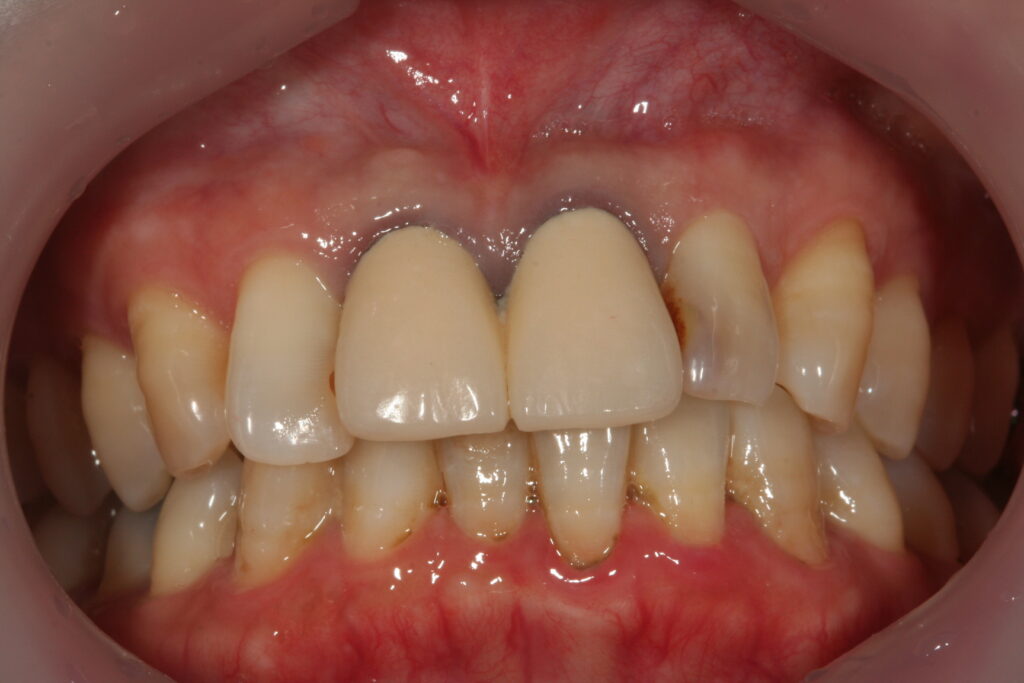

審美治療 2015.09.26 症例紹介 10年以上前から前歯の見かけが気になっておられました。1回目:カウンセリング2回目:治療、型取り、仮の歯3回目:取り付けて終了 でした。 症例紹介 都市伝説、、、、、前の記事 歯石とは?次の記事